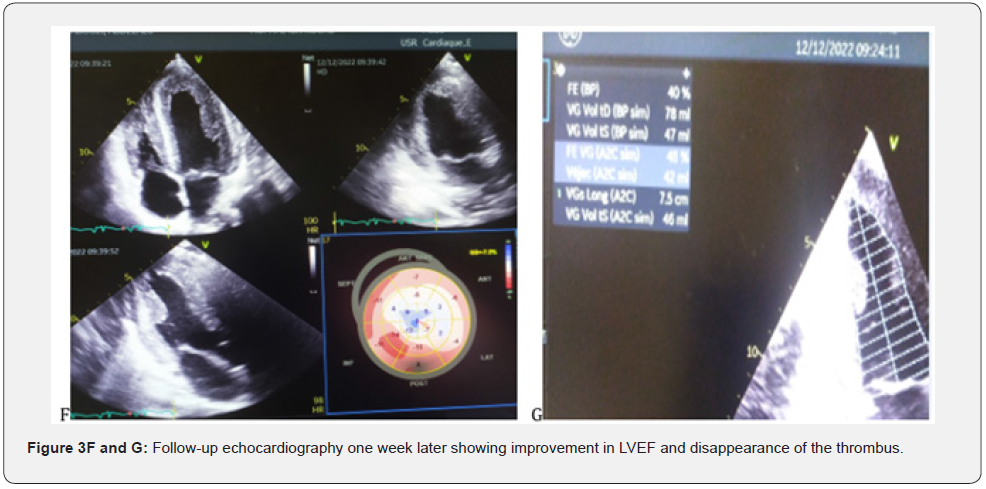

Echocardiography showed a non-dilated, slightly hypertrophied LV with severe dysfunction and 20% EF, with a huge mobile thrombus measuring 42 x 23 mm in the LV, no significant mitro-aortic valve disease.The MRI scan showed a late subpericardial enhancement in severe bi ventricular dysfunction with a huge mobile intra LV thrombus suggesting acute myocarditis. The patient was put on strict rest and an IV diuretic treatment with monitoring of the diuresis, an effective anti-coagulation, a bolus of solumedrole 120 mg over 3 days and per-os relay of 60 mg with progressive degression. The evolution was marked by a clear regression of the congestive signs, an improvement of the general state of the patient over 7 days and a recovery of the EF to 40% vs 20 at admission. A disruption of the thrombus after 7 days of anti-coagulation with a minimal migration giving a light splenic and hepatic infarction without significant clinical repercussions. The patient was discharged after 12 days in hospital on Coversyl 5 mg/d; Cardensiel 2.5 mg/d; Sintrom 7.5 mg/d and Solupred 60 mg/d with a 3 month tapering programme.

Myocarditis is an inflammatory disease of the myocardium defined by the Dallas histological criteria. Diagnosis requires the demonstration of a predominantly lymphocytic myocardial inflammatory infiltrate defined by the presence of >14 leukocytes/mm3 including more than 4 monocytes > mm3 and 7 CD3+ T lymphocytes/mm3, associated with myocyte necrosis of non-ischaemic origin [4]. The pathophysiological hypotheses are variable and include both cell lysis related to direct viral toxicity, and inflammatory phenomena related to the activation of the innate immune response (production of pro-inflammatory cytokines) and then specific cellular response [5- 6]. In certain situations, this activation may be excessive and lead to significant destruction of the cardiomyocytes, causing left ventricular dysfunction as seen in our patient, which can evolve into a state of cardiogenic shock if not managed immediately, which worsens mortality in the most severe forms (fulminant myocarditis). In all cases, this cardiomyocyte necrosis is responsible for the elevation of troponin, as confirmed in our patient with troponin levels of 300 mg, which is a key element in the diagnostic suspicion without any electrical sign of myocardial suffering of ischaemic origin [7]. The clinical phenotype of myocarditis is very polymorphic, which makes its positive diagnosis difficult; the diagnosis is suspected in the presence of clinical symptoms associated with an elevation of the tropo-nine and possibly inflammatory markers. The picture of acute heart failure corresponds to the appearance of signs of heart failure over a period of less than two weeks. This picture of fulminant myocarditis is often preceded a few days before by an influenza-like episode, which is consistent with our presentation where we find a history of influenza-like illness favoured by an unfavourable socio-economic level in our third world countries. The left ventricular dysfunction can be severe and responsible for shock because of diogenesis. Echocardiography usually shows a non-dilated, hypertrophied left ventricle (in relation to myocardial oedema) in our patient we find a slight hypertrophy at 10 mm of the wall and 10 mm of the IVS (Figure 1 A & B) with altered systolic function [8] as well as severe LV dysfunction in our patient with an EF of 20% (Figure 1C). Myocardial magnetic resonance imaging (MRI) has become an indispensable non-invasive examination in the management and follow-up of myocarditis (Figure 1D & E). The diagnosis of myocarditis is based on the presence of two of the following three Lake Louise criteria [9] : Myocardial hyperhaemia, demonstrated by early global gadolinium enhancement of the myocardium in a T1-weighted sequence; regional or global myocardial oedema, demonstrated by hyper signal in a T2- weighted sequence; myocardial necrosis or fibrosis, most often multifocal, in the pericardium, as seen in the images of our patients (Figure 3 F and G), demonstrated by late gadolinium enhancement in a T1-weighted sequence. The presence of a pericardial effusion is an additional argument for the diagnosis of myocarditis which further supports the diagnosis in our patient with the pericardial effusion slide found on MRI. For the treatment in the general case, the recommendations of the ESC are to propose in first intention a symptomatic treatment of the cardiac insufficiency by the diuretic for the decongestion; the IEC and beta blockers for their effects anti-remodelling. Studies concerning the curative treatment of myocarditis mainly concern chronic forms, which are known to have an unfavourable evolution in the medium and long term, with progressive degradation of cardiac function. The diagnosis is then made during biopsies carried out in the context of recently discovered dilated cardiomyopathy. Various immunosuppressive treatments (prednisolone, cyclosporine, cyclophosphamide) have been tried in myocarditis. In a recent prospective randomised double-blind study comparing placebo versus prednisone and azathioprine in 85 patients with non-viral chronic lymphocytic myocarditis who had symptoms of heart failure for more than six months despite conventional medical treatment (TIMIC Study), In the TIMIC Study, an improvement in left ventricular ejection fraction (LVEF) and a reduction in left ventricular enddiastolic volume were found in 88% of the 43 patients treated, whereas cardiac function deteriorated in 83% of the 42 patients who received placebo [10-12]. In the light of these studies, we recommended that patients be treated with bolus corticosteroids (solumedrole 120) as an adjuvant to the corticosteroids, and we noted a favourable evolution under treatment with a good clinical and echocardiographic improvement (Figure 3 F and G).